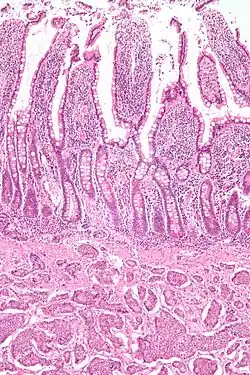

| Picture of a carcinoid tumour that encroaches into lumen of the small bowel. Pathology specimen. The prominent folds are plicae circulares, a characteristic of small bowel. | |